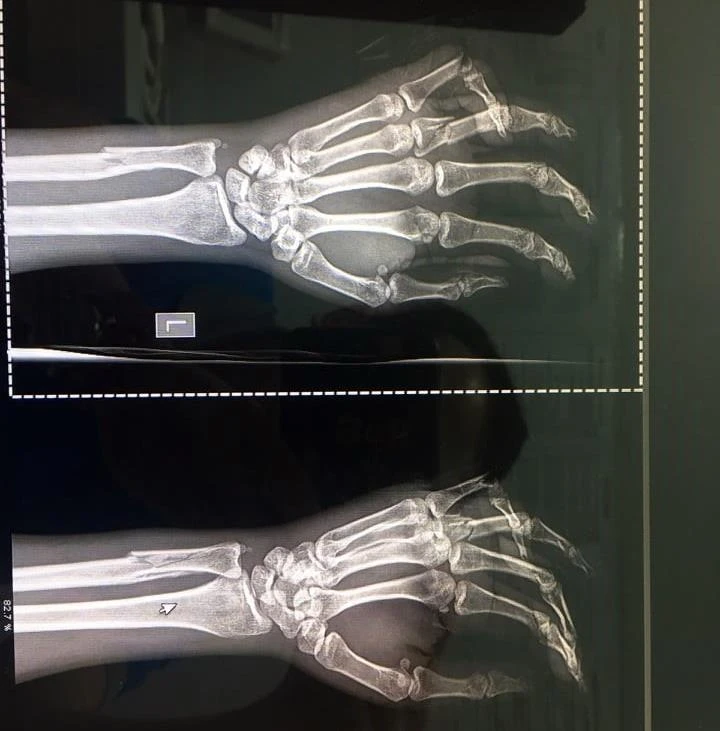

Theo BV Chợ Rẫy, bệnh nhân bị chấn thương đầu, vỡ nền sọ (gãy xoang sàng hai bên); cả tay trái và phải bị gãy xương trụ, xương quay, xương mác; gãy nhiều xương ngón tay ở bàn tay trái… Đặc biệt nạn nhân đang có thai sống khoảng 26 tuần.

Cả tay và chân nạn nhân đều bị gãy.